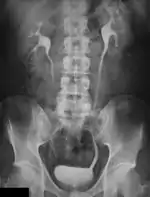

Digital Subtraction Angiography (DSA), as the name implies, involves an image subtraction technique - see Figure 7.1. As will be seen below, the technique involves more than simply applying a subtraction process in the digital image processor. In addition, it will be seen that the type of technology utilised, while based on the design of fluoroscopy systems, needs to incorporate a number of modifications unique to DSA. Before addressing the technology however, some basic physics needs to be introduced which will aid in putting the subsequent technology discussion into context.

- Additional processes involve Bolus Chasing, Rotational Angiography and Volume Tomographic Angiography. Bolus Chasing[28] has been found to be particularly helpful in peripheral angiography, for example. Here, the progress of the contrast medium is tracked automatically and used to increment the table and/or XRT/image receptor movement to the next anatomical region. The subsequent set of subtraction images can then be used to construct a composite image of the peripheral vasculature. In Rotational Angiography[29], a C-arm assembly, for example, can be caused to rotate at 10 - 30 degrees per second during the imaging sequence. Subsequent dynamic display of the subtraction images can be used to generate a perceived 3D presentation so that complex relationships within the vasculature can be more readily appreciated. Volume Tomographic Angiography[30] is similar to Computed Tomography (CT) where the C-arm is rotated around the patient during the imaging sequence. The image data is subject to a volume reconstruction algorithm which permits generation of three-dimensional images of the opacified vasculature. We will consider this latter process in more detail below.